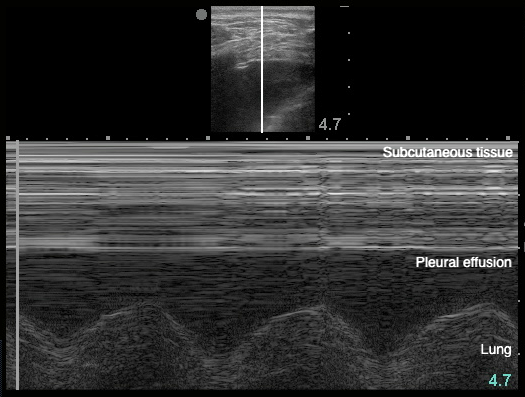

- Sinusoid sign: represents movement of lung within the effusion22

- Figure 20. Sinusoid sign

- Demonstrates fluctuating distance between visceral and parietal pleura during respiratory cycle

- Volume of the effusion can be measured,28,83-85 more effectively than with CXR.28 A quick and easy method uses the largest distance between parietal and visceral pleura at end-expiration.83

- Figure 21. Estimation of pleural effusion volume